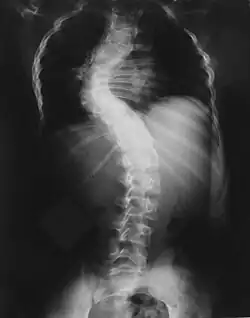

Im Altersbereich bis zu 12 Jahren kann es zu Verformungen der Wirbelkörper kommen, die zu einer schweren Skoliose führen können. Eine frühzeitige und regelmäßige Vorstellung bei einem mit NF1 vertrauten Spezialisten ist daher ratsam.

Skelettveränderungen treten bei einem Drittel der Patienten auf und bringen die Neurofibromatose-Patienten zum Orthopäden.

Sehr häufig finden sich Wirbelsäulenveränderungen von einfacher über kurzbogiger und knickförmiger Skoliose bis extrem ausgeprägten Kyphoskoliosen aufgrund von Fehlentwicklung der Wirbelkörper.[16]